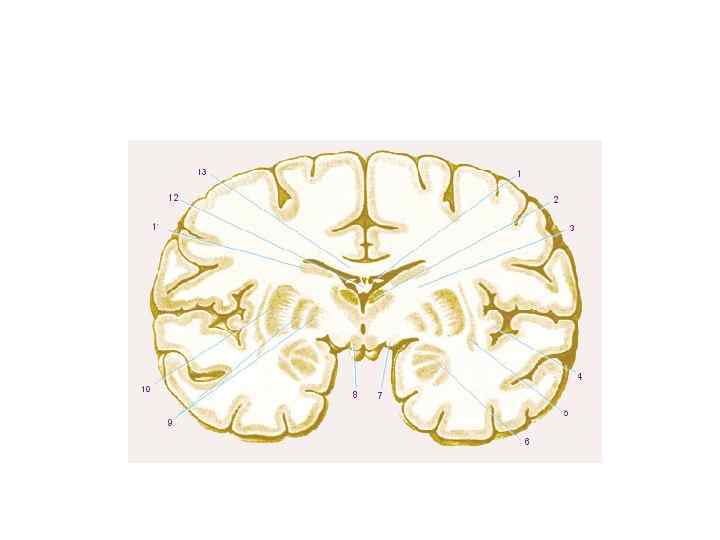

Тела нейронов - основа серого вещества ЦНС: Ø кора больших полушарий Ø кора мозжечка Ø ядра ствола, мозжечка, подкорковые ядра Отростки нейронов образуют белое вещество ЦНС, нервы и их производные ПНС.

Тела нейронов - основа серого вещества ЦНС: Ø кора больших полушарий Ø кора мозжечка Ø ядра ствола, мозжечка, подкорковые ядра Отростки нейронов образуют белое вещество ЦНС, нервы и их производные ПНС.

ПОЛОСАТОЕ ТЕЛО • ХВОСТАТОЕ ЯДРО • ЧЕЧЕВИЦЕОБРАЗНОЕ ЯДРО Ø СКОРЛУПА Ø БЛЕДНЫЙ ШАР

ПОЛОСАТОЕ ТЕЛО • ХВОСТАТОЕ ЯДРО • ЧЕЧЕВИЦЕОБРАЗНОЕ ЯДРО Ø СКОРЛУПА Ø БЛЕДНЫЙ ШАР